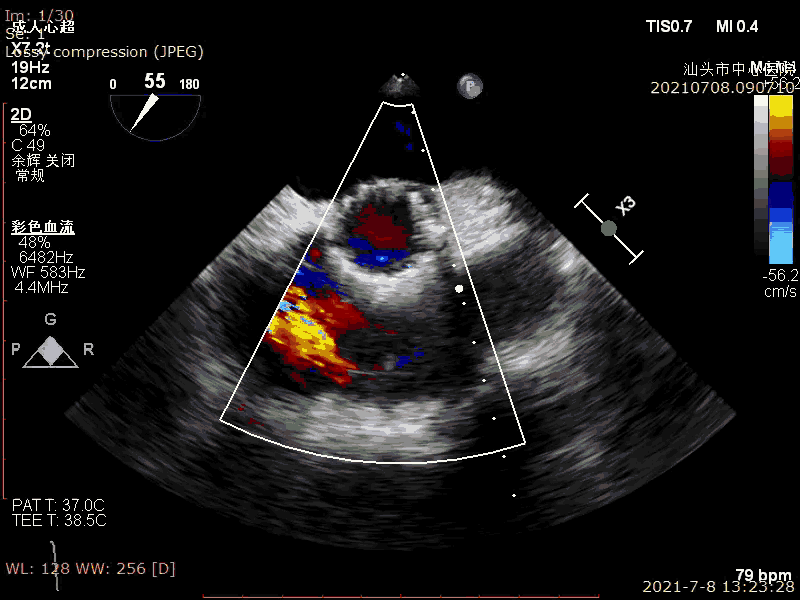

超声示:

LVEF:63%

重度主动脉瓣狭窄并轻度反流

术前超声

术后超声